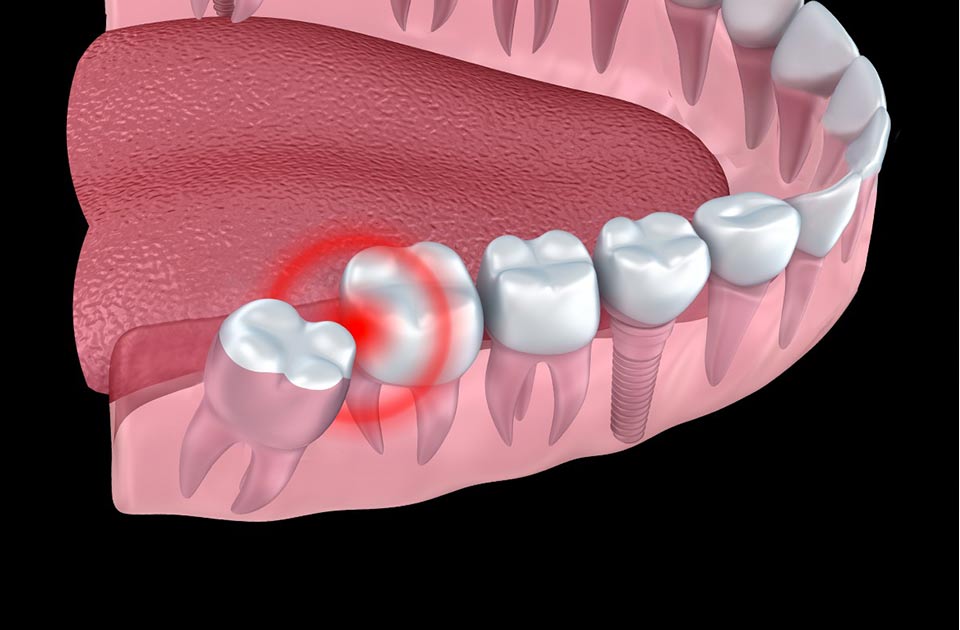

برخی از علائم و نشانه ها هستند که می توانند خبر از دندان عقل نهفته شما بدهند که نیاز به کشیدن دارند عبارتند از :

درد یا حساسیت دندان

لثه های متورم و باد کرده

ازدحام و شلوغی بیش از حد دندان ها

نهفتگی مزیال : در این رویش ، دندان عقل اگر تاج دندان به عقل به سمت جلوی دهان زاویه پیدا کند به آن دندان نهفته مزیال می گویند .